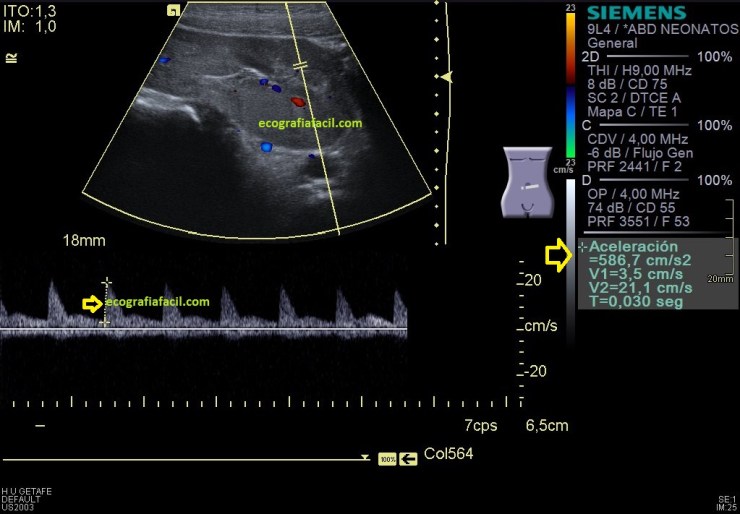

En la imagen 11 vemos una valoración cuantitativa en doppler espectral con valores señalados de 840 cm/sg de aceleración, que es muy importante que esté en valores superiores a 300 cm/sg para ser normal y se mide en la fase de sístole, al comienzo, en la primera pendiente, que corresponde con la R del trazado electrocardiográfico, hasta que esta pendiente llega a lo más alto o hace una ligera bajada. Observa en la imagen 11 donde se hace la medida y compara con la imagen 14, cómo el espectro es diferente, es normal.

Las imágenes 12,13 y 14 son el doppler y el doppler pulsado del riñón izquierdo, que aunque malrotado y ectópico mantiene un aspecto normal tanto en modo B, como en el doppler color y en el modo angio o doppler power. El espectro es normal, con valores de aceleración superiores a 300 cms/sg.